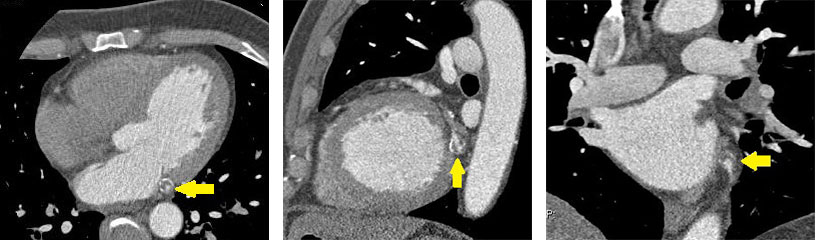

По данным КТ (Philips Ingenuity 128) на 2-е сутки госпитализации: умеренный кальциноз КА, индекс Агатстона 230; фузиформная аневризма в средней трети огибающей ветви левой КА 11×9,5 мм протяжённостью 16 мм с кальцинозом стенок и пристеночными концентрическими тромботическими массами, остаточный просвет 3,7 мм (рис. 1, 2); стеноз в проксимальной трети передней межжелудочковой ветви 50–55%, стеноз в проксимальной трети огибающей ветви левой КА 60–65%.

Рис. 1. Компьютерная томограмма, мультипланарная реконструкция. Фузиформная аневризма в средней трети огибающей ветви левой коронарной артерии с кальцинозом стенок и пристеночными концентрическими тромботическими массами (отмечена стрелкой)

Рис. 2. Компьютерная томограмма. Фузиформная аневризма в средней трети огибающей ветви левой коронарной артерии с кальцинозом стенок и пристеночными концентрическими тромботическими массами (отмечена стрелкой)